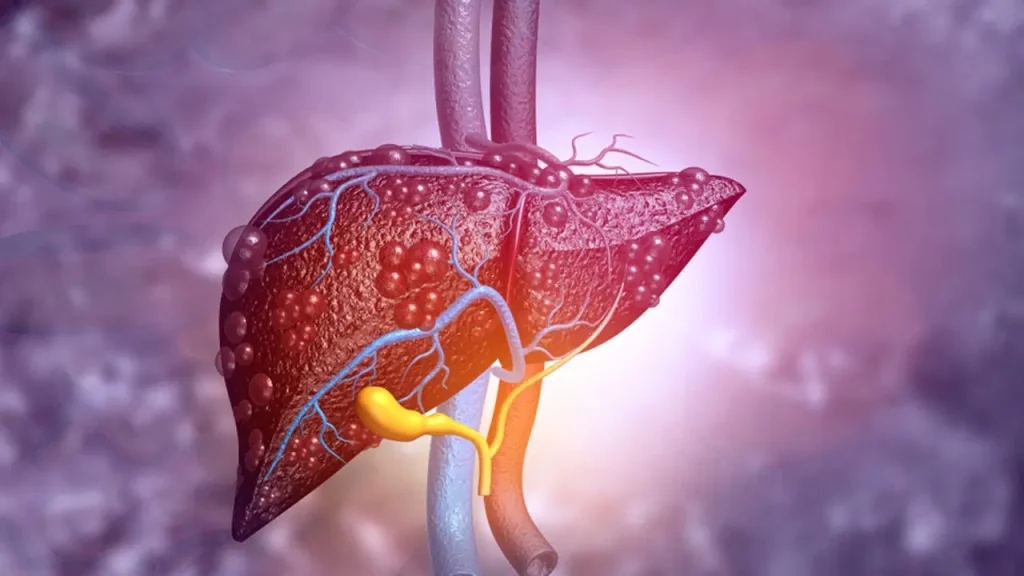

Karaciğer yağlanmasının karaciğer hücrelerinde normalden fazla yağ birikmesiyle oluştuğunu söyleyen Uzm. Dr. Göktürk, “Karaciğerin ağırlığının yüzde 5 ila 10’undan fazlası yağdan oluştuğunda, bu durum karaciğer yağlanması olarak adlandırılır” diye konuştu.

Tedavi edilmeyen karaciğer yağlanmasının iltihaplanma (NASH) ve fibrozis gelişimine yol açabileceğini belirten Dr. Göktürk, “Bu durum ilerlerse siroz ve karaciğer yetmezliği hatta karaciğer kanseri gelişebilir. Ancak düzenli kontroller ve sağlıklı yaşamla bu tablo önlenebilir” dedi.